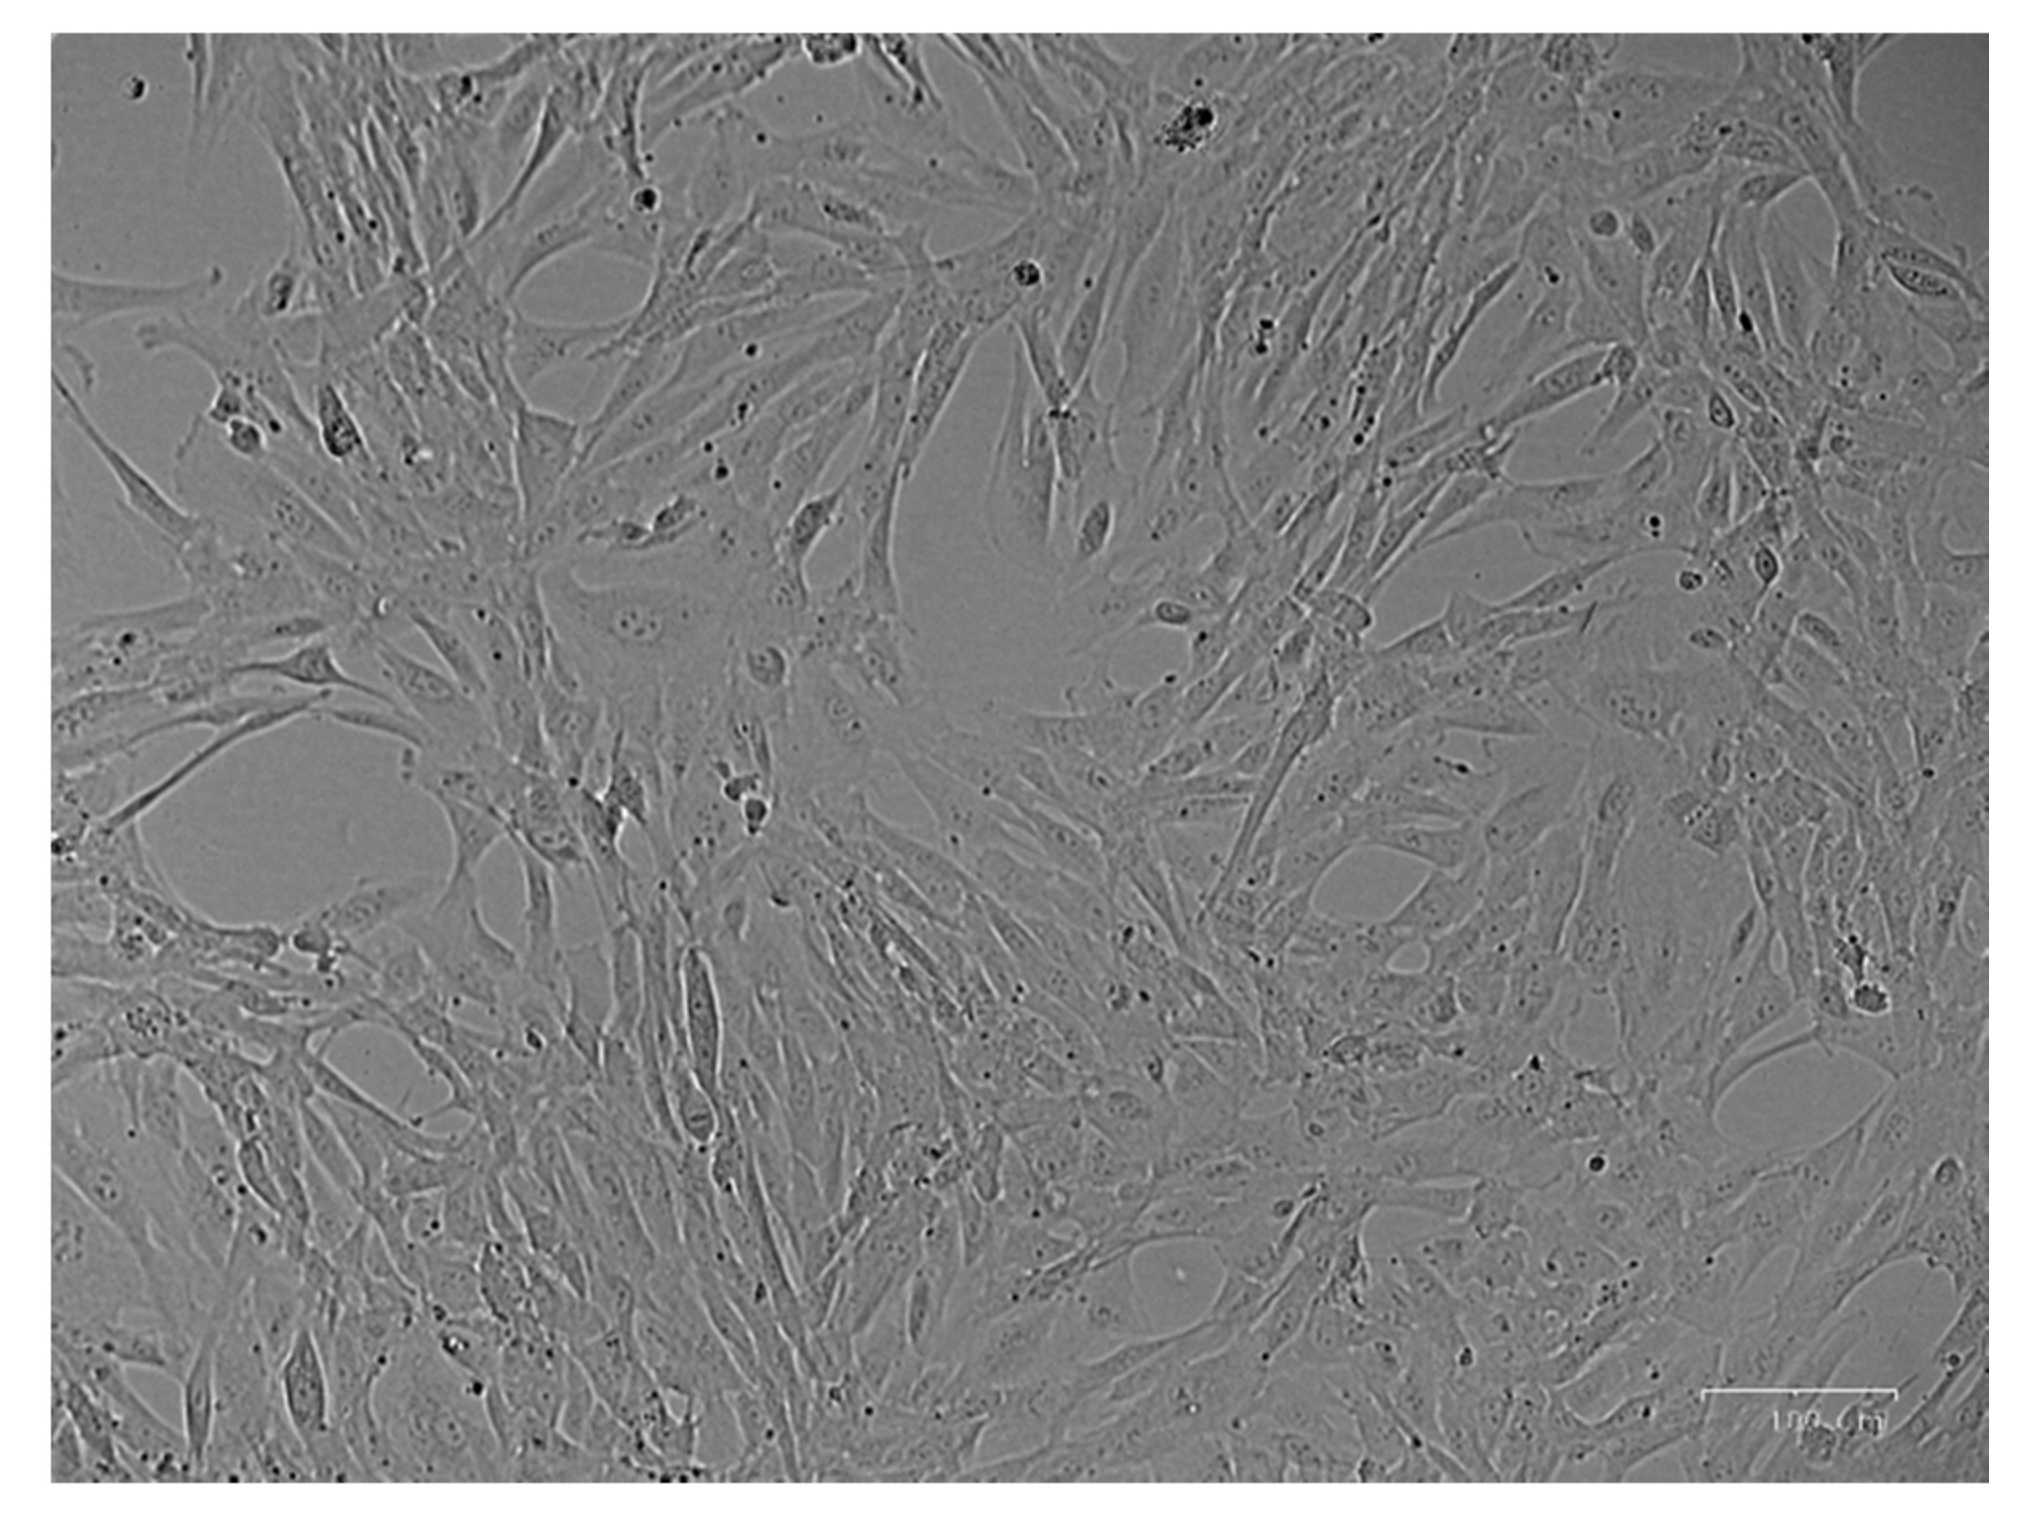

3.1. Cell Culture Isolation